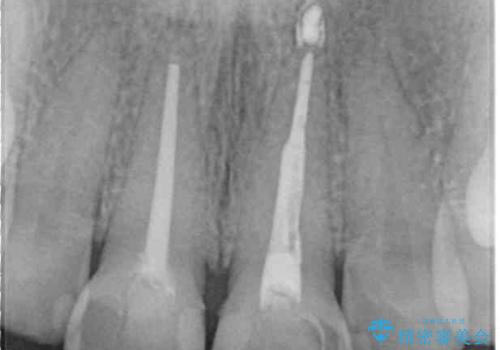

- 前歯の形と色を気にして来院された患者様です。

虫歯で神経を取り除いたことによる変色や充填物の着色などが認められたため、オールセラミッククラウンにて補綴することとしました。

また、咬耗により周囲の歯がすり減ったことで、前歯2本のみが長く見えていたため、周囲に長さを合わせることとしました。